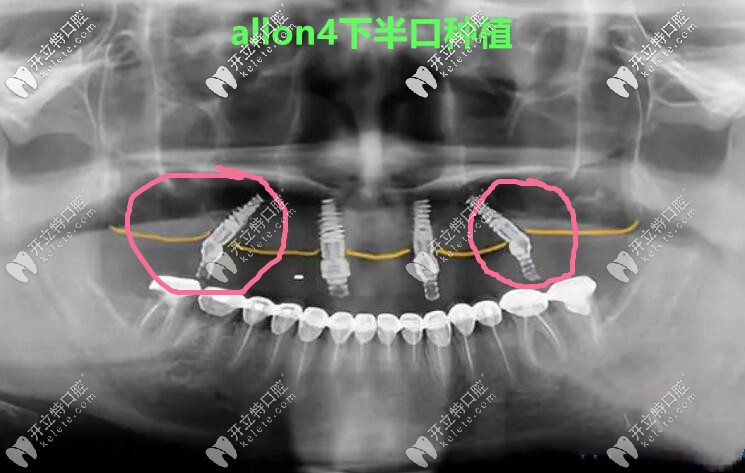

張海波院長(zhǎng)說(shuō),它倆明顯的區(qū)別就是,allon4/6有2顆植體是斜著的,因?yàn)楸荛_(kāi)了神經(jīng)管和上額竇孔腔,所以主要針對(duì)的是那些牙槽骨非常糟糕,無(wú)法常規(guī)種植的人。

做allon4下半口種植牙真人案例CT照↓↓↓

做allon4下半口種植牙真人案例CT照